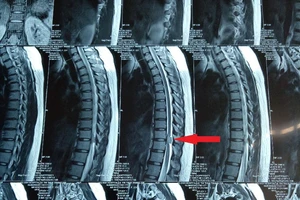

phim chụp u tủy

Hình ảnh phim chụp trước và sau phẫu thuật khối u tủy nguyên nhân gây liệt đôi chân của bệnh nhân. Ảnh: BVCC

Tại bệnh viện, kết quả thăm khám và chụp cộng hưởng từ cho thấy bệnh nhân bị u tủy trong đốt sống ngực. Khối u ngoài màng cứng gây chèn ép vào tủy sống.

Bệnh nhân được chỉ định phẫu thuật cấp cứu để loại bỏ khối u tủy, giải chèn ép tủy. Kết quả giải phẫu bệnh khối u cho thấy đó là khối u lành tính.